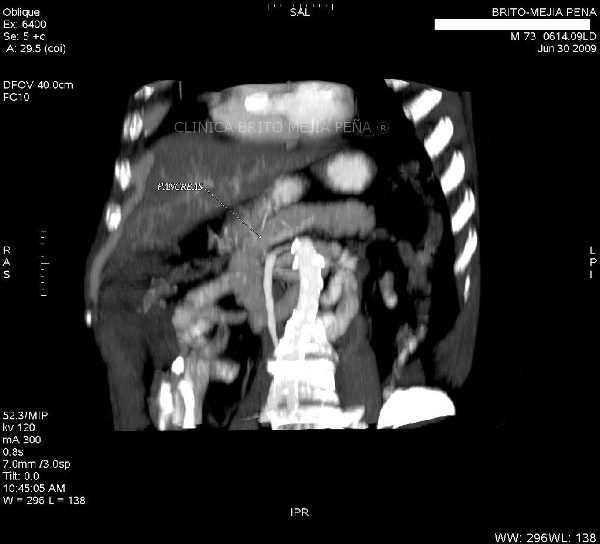

Páncreas normal MPR